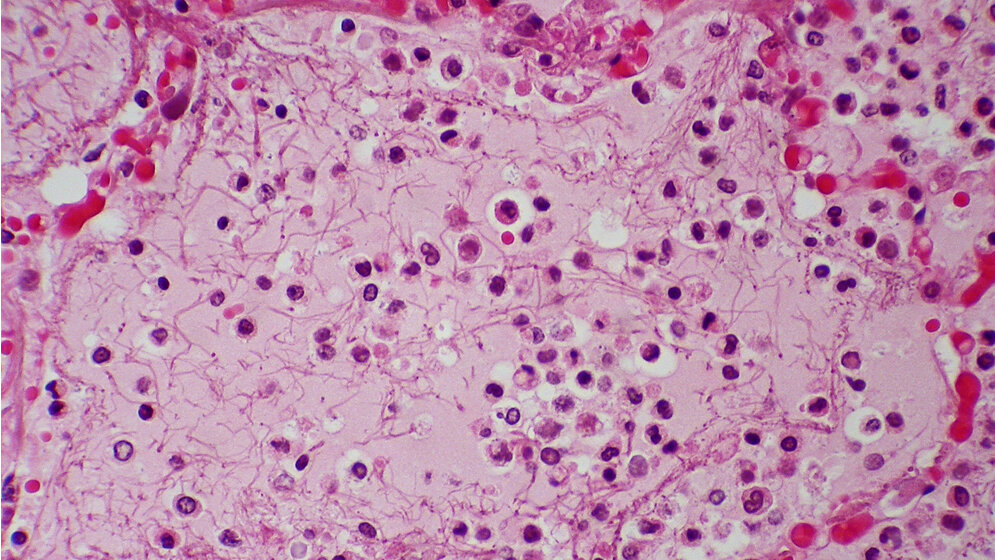

Die ambulant erworbenen und nosokomialen Pneumonien zählen zu den häufigsten im Krankenhaus behandelten Infektionserkrankungen. Jüngere profitieren von der Pneumokokken-Impfung. Zur Basisdiagnostik einer Pneumonie zählt die Durchführung eines Thoraxröntgenbildes in 2 Ebenen. In einer Studie zur Ermittlung prädiktiver Laborparameter für bakterielle und virale Pneumonien bei Kindern und Jugendlichen zeigte sich, dass nur das CRP ein wirklich unabhängiger, für sich allein aussagekräftiger Parameter war. Bei Betrachtung des Procalcitonins zeigte sich, dass PCT eher für die Abschätzung der Schwere der Erkrankung genutzt werden kann.